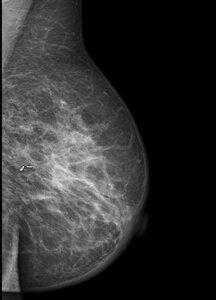

В операционной мы проводим контроль ширины краёв резекции на специальной рентгенологической установке:

Светлый поясок неизменённых тканей говорит о достаточной ширине отступа от опухоли.